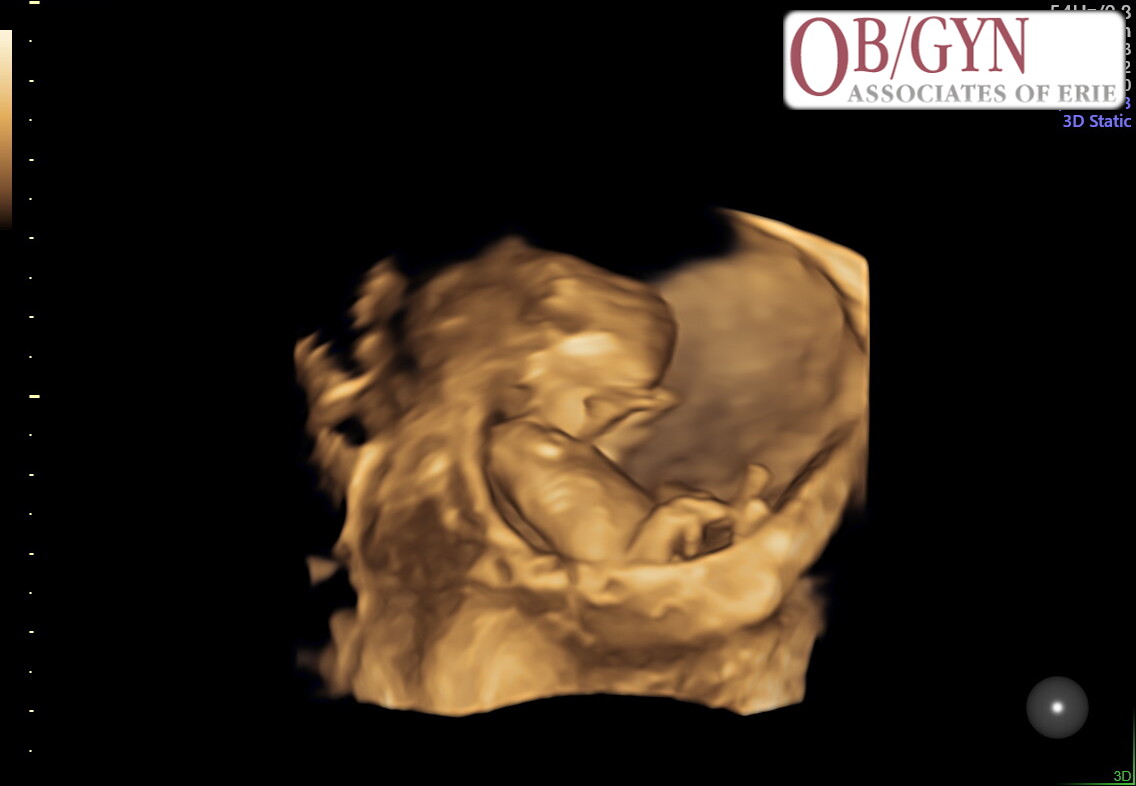

Awaiting the arrival of

Baby LaVette